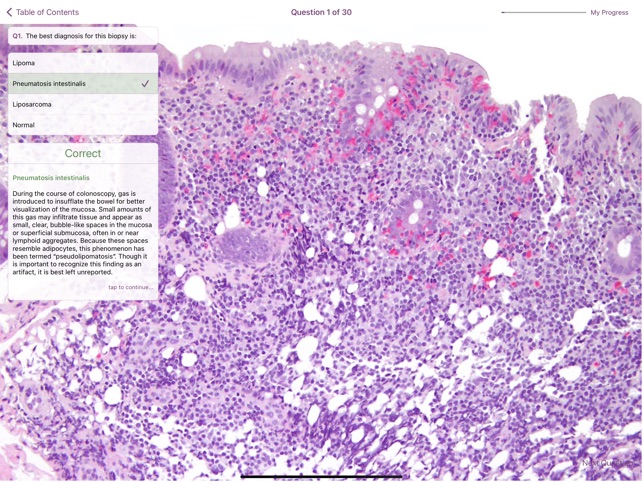

Developed by The Johns Hopkins University Department of Pathology, this educational resource functions as a digital atlas of colonic pathology. The platform provides a comprehensive visual reference covering normal histology alongside a range of neoplastic and non-neoplastic disease entities. The system presents high-resolution gross and microscopic images, each annotated with a diagnosis, a descriptive caption, and a list of key diagnostic features. A flash card module enables the creation of customized study decks from the integrated image bank. The application also includes a self-assessment component, which utilizes an image-based quiz with multiple-choice questions.

The application is designed for pathology residents, fellows, and practicing pathologists as a specialized pedagogical tool for the study of colonic diseases. Its primary utility is to provide a structured visual repository for training and self-study, encompassing inflammatory disorders, polyps, and various tumors. This app is designed to supplement learning and may be most effective when used alongside formal instruction.